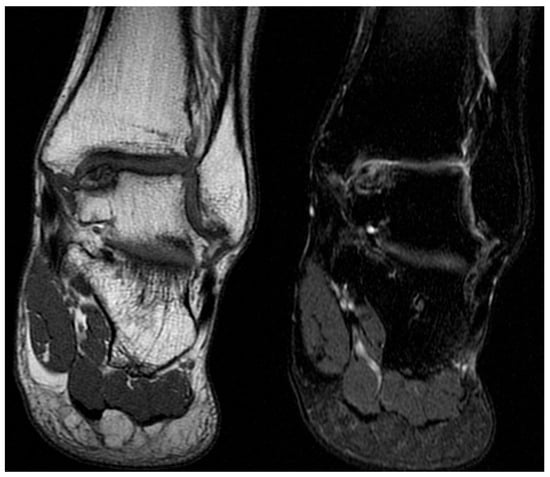

Diagnosis is based on patient history and clinical presentation. In most cases, the clinical presentation alone is adequate to establish the diagnosis, and imaging is not routinely required during the initial stages of the condition. First-line imaging studies include plain radiographs for differential diagnosis; however, they are not diagnostic, as a fragmented calcaneus can also be observed in asymptomatic children (Figure 2). The nucleus, in addition to being fragmented, may also be physiologically thickened, bipartite, smaller, or displaced upwards or downwards, without having any pathological relevance [14]. Diagnosis is further supported by magnetic resonance imaging (MRI), which can demonstrate bone marrow edema, microfractures, and stress-related bone responses [13] (Figure 3 and Figure 4).

Eleven-year-old male patient. Radiograph (left) demonstrating typical fragmentation and bipartite appearance of the calcaneal apophysis. MRI (right) showing detailed fragmentation with associated bone marrow edema.

Figure 4.

Ten-year-old male patient. Radiograph (left) revealing marked fragmentation, thinning, and bipartition of the calcaneal apophysis. MRI (right) demonstrating extensive associated bone marrow edema.